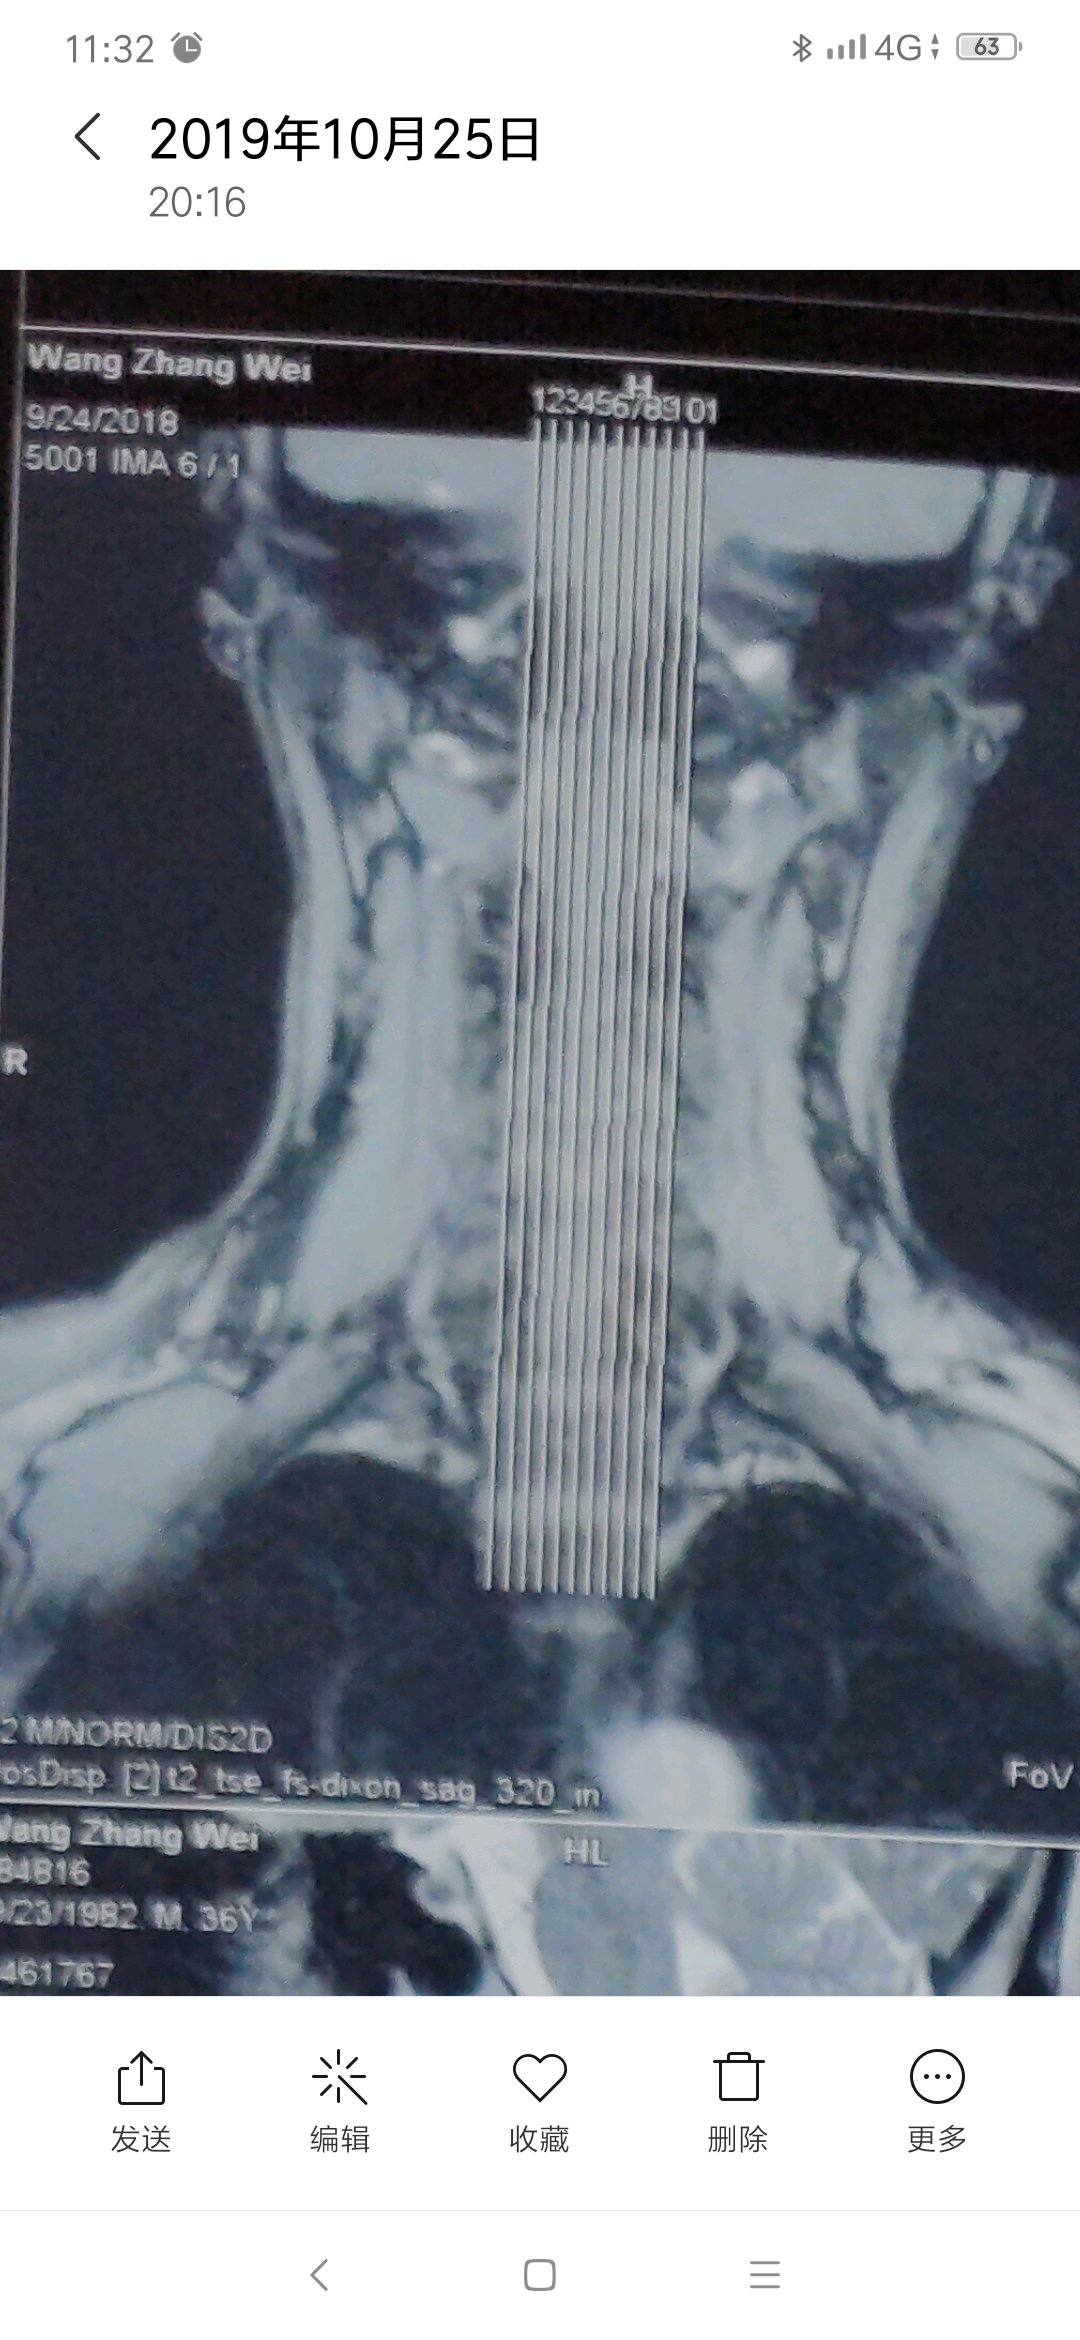

有专家吗,这个层度严重吗,怎么能治好,主要表现脖子疼痛,活动受限。

片子不严重,多锻炼就好了

每次去医院看病,医院都说不严重,可是痛起来真的太痛苦了。